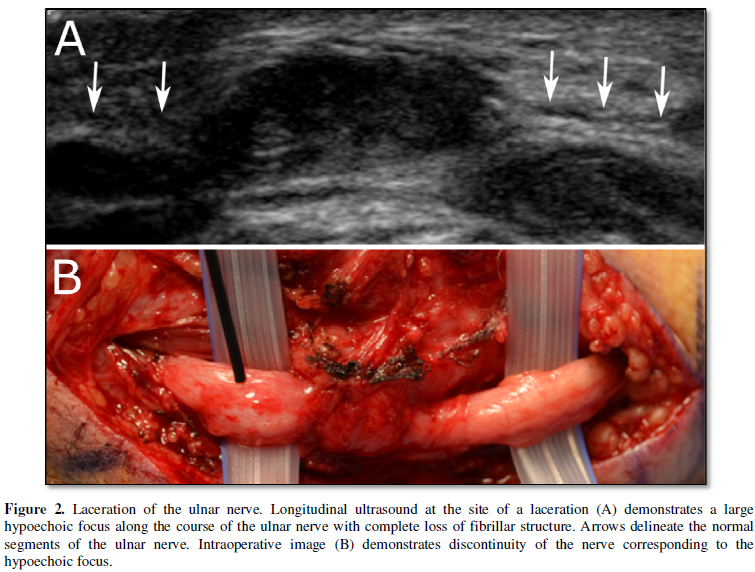

In long axis, the hypoechoic nerve fibers are oriented in parallel along

the long axis of the nerve, again separated by the more echogenic perineural

connective tissue. When injured, there is disruption of the normal fascicular

architecture of the nerve and, with increasing degree of injury, enlargement of

the nerve and discontinuity of the fibers [4] (Figure 2). In cases of compressive neuropathy, the nerve develops

an “hour-glass morphology” when seen in long axis, with the nerve swelling